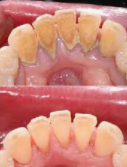

치과의사 선생님의 이야기를 들어본 결과 내려앉은 잇몸은 다시 올리는건 어려우며 현재를 유지하는 방법이 최선이라고 합니다. 잇몸 내려앉음 치료방법에는 앞서 소개된 원인 중 하나인 치석을 제거하는 방법입니다. 위에 오른쪽 사진을 보시면 스케일링 전/후 인데요. 오른쪽 스케일링 후 사진을 보면 치석을 제거하니 치아 사이사이 비어있는 모습이 보입니다. 이렇듯 치석이 많이 끼게되면 잇몸이 내려앉기 때문에 치석이 많이 끼이기 전에 스케일링을 받는 것이 좋습니다. 스케일링은 1년마다 1번씩 보험처리가 가능하기 때문에 1년에 1번 스케일링을 꾸준히 받아주시는게 좋습니다.